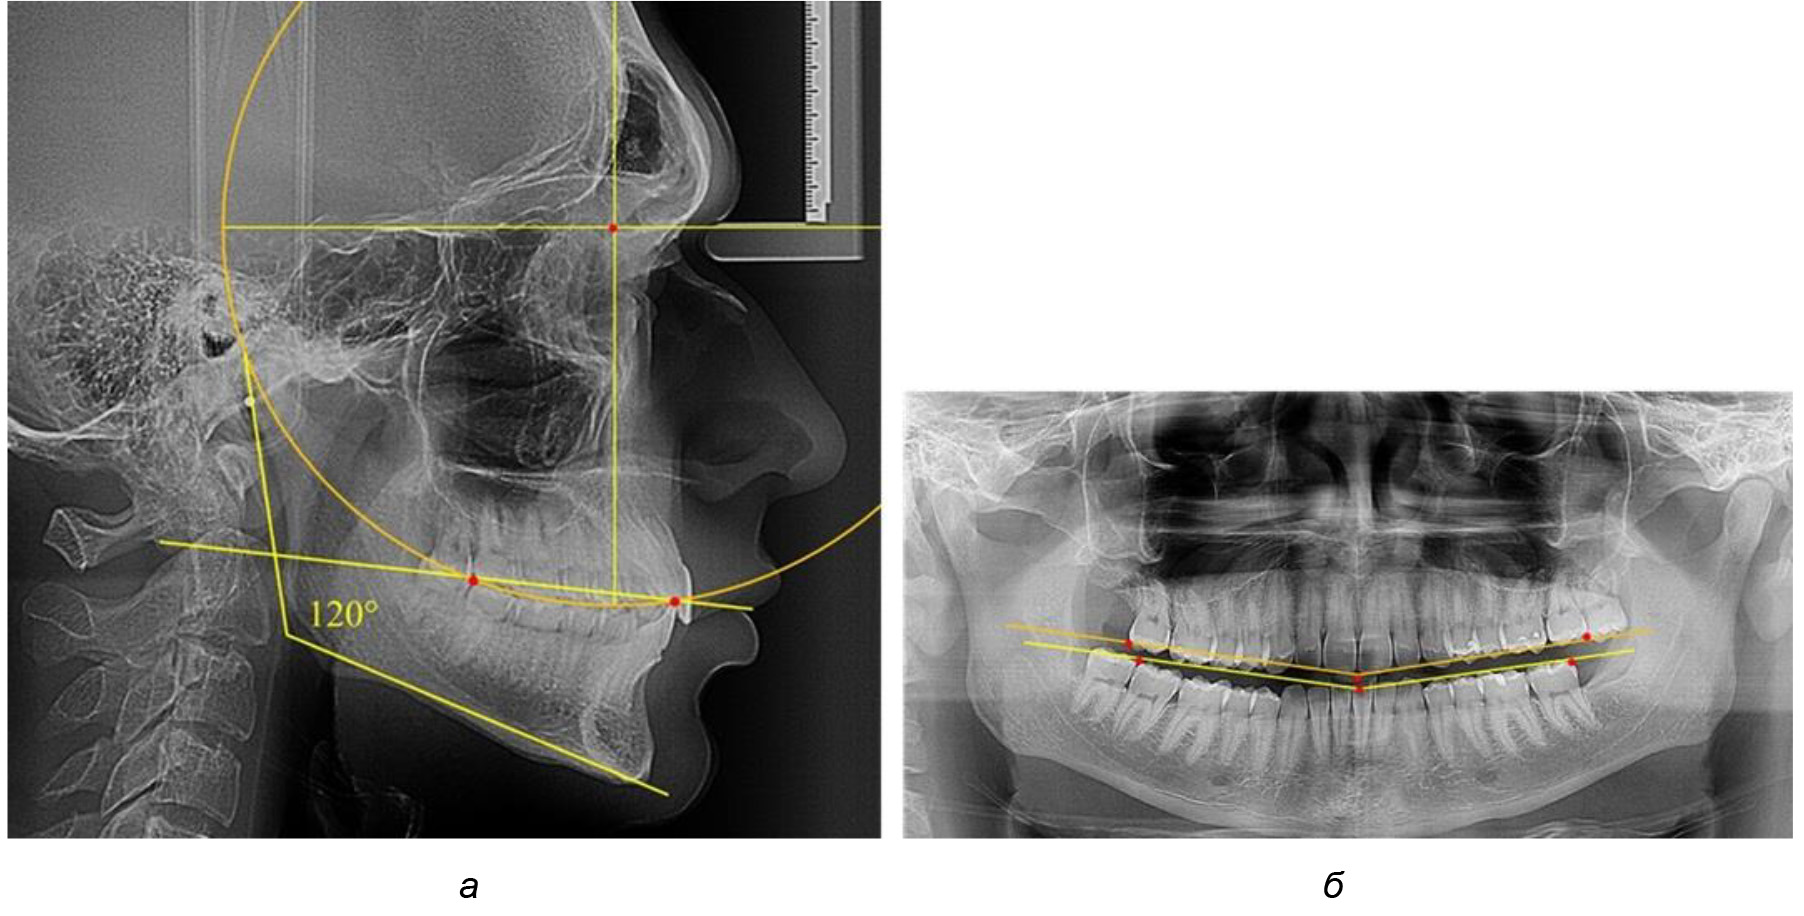

В 3-ю подгруппу вошли ТРГ и ОПТГ 14 человек 1-й группы, что составило (22,58 ± 5,31) % от общего количества людей 1-й группы. Величина угла нижней челюсти в среднем составила (114,85 ± 2,87)° и характеризовала горизонтальный тип нижней челюсти.

Глубина кривой Spee в среднем по 2-й подгруппе составил (2,94 ± 0,47) мм, что было меньше, чем в других подгруппах. Деление величины радиуса круга к длине окклюзионной линии составило 1,616 ± 0,02 (рис. 4).

Рис. 4. Особенности кривой Spee на ТРГ (а) и ОПТГ (б) у людей с горизонтальным типом лица

Обращает на себя внимание, что глубина кривой Spee в анализируемой подгруппе практически не отличалась от показателей, полученных у людей с физиологической окклюзией, и составляла (4,23 ± 1,58) мм. Отношение радиуса окружности к сагиттальному размеру окклюзионной линии в среднем по подгруппе составляло 1,623 ± 0,02 и соответствовало числу Фибоначчи.

После лечения пациентов техникой «прямой» дуги, так же как и в 1-й подгруппе, было отмечено увеличение сагиттального размера окклюзионной лини в среднем на (2,38 ± 0,83) мм. Окклюзионная линия практически касалась окклюзионного контура всех жевательных зубов, и отмечалось практически полное отсутствие кривой Spee, так же как и у людей 1-й подгруппы 2-й группы (рис. 6).

Рис. 6. Особенности ТРГ при оптимальной кривой Spee до лечения (а) и после лечения (б) техникой «прямой» дуги

Таким образом, проведенное лечение техникой «прямой» дуги способствует нормализации окклюзионного равновесия и торку передних зубов, однако не соответствует оптимальному окклюзионному статусу, характеризующему физиологическую окклюзию. При этом величина нижнечелюстного угла оставалась на прежнем уровне.